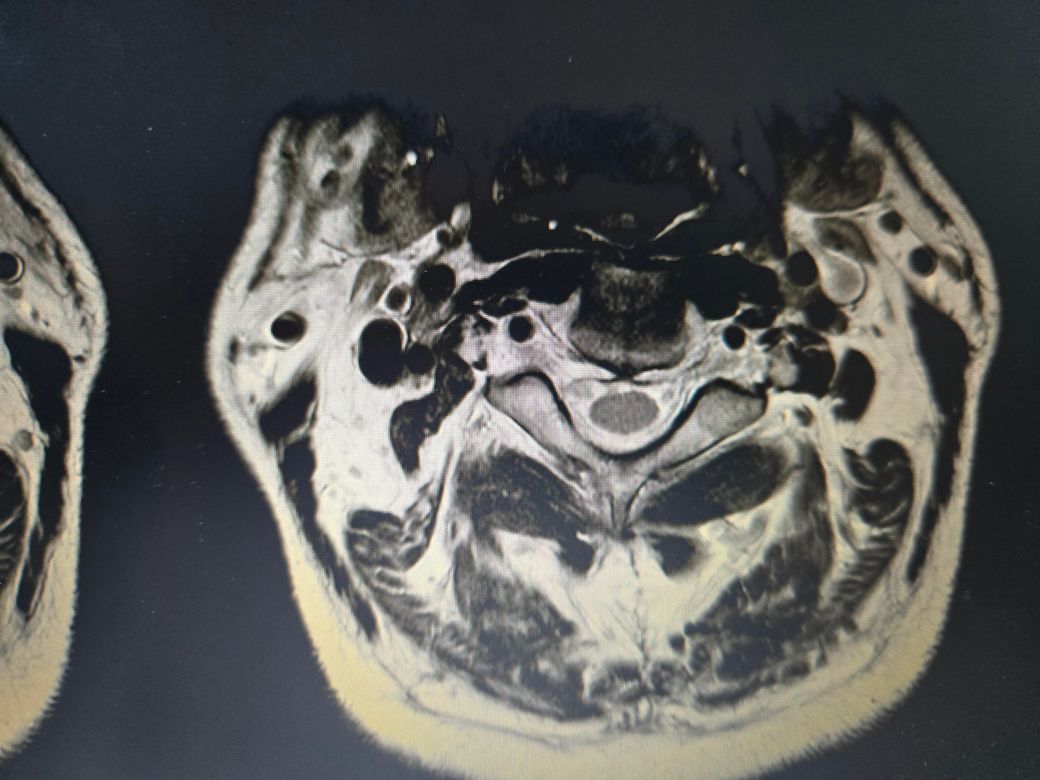

목디스크, 협착증 수술안해도되는건가요

목디스크 협착

정형외과에서는 디스크 협착증소견을 내고서는 마사지 잘하면된다는데, mri상으로도 심하지 않은건지궁금합니다

• 3번 째 사진